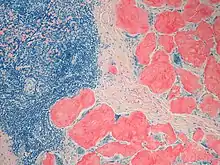

Example of amyloid deposits under Congo Red staining

LECT2 amyloidosis is diagnosed by a kidney biopsy which reveals two key findings: a) histological evidence of Congo red staining material deposited in the interstitial, mesangial, glomerular, and/or vascular areas of the kidney and b) the identification of these deposits as containing mainly LECT2 as identified by proteomics methodologies. Kidney biopsy shows the presence of LECT2-based amyloid predominantly in the renal cortex interstitium, glomeruli, and arterioles.[17][1] LECT2 amyloidosis can be distinguished from AL amyloidosis, the most common form of amyloidosis (~85% of total cases), by testing their blood for the presence of high levels of a clonal immunoglobulin light chain. If the patient tests negative for this light chain, positive Congo Red staining of the kidney biopsy strongly suggests LECT2 amyloidosis.[1][11]